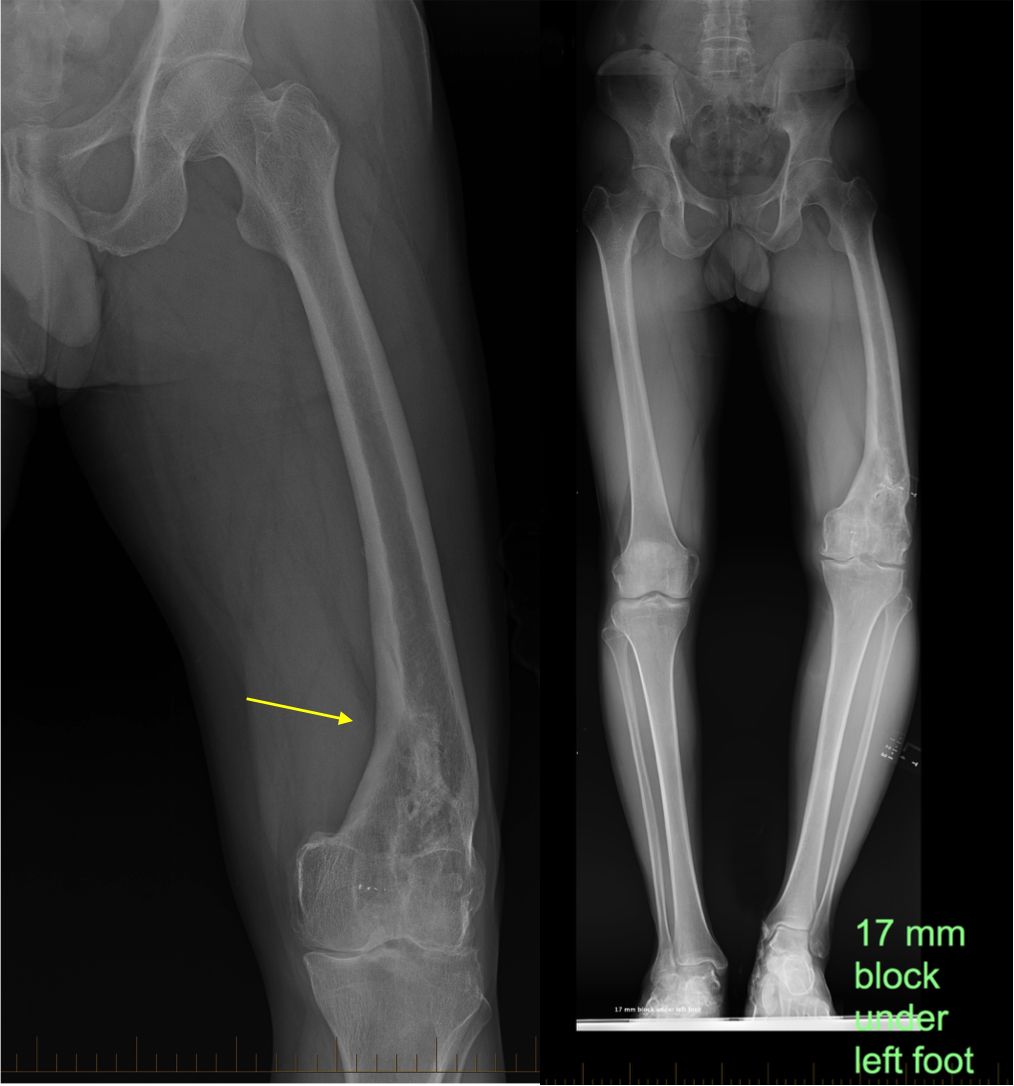

malunion and leg length discrepancy

(Left) X-ray shows a patient who sustained a broken left thighbone that healed with a malunion (yellow arrow). (Right) This scanogram shows the same patient standing on wooden blocks to equalize leg length. As a result of the malunion, the patient’s left leg is bowed and is approximately 17 mm (3/4 inch) shorter than the right leg.